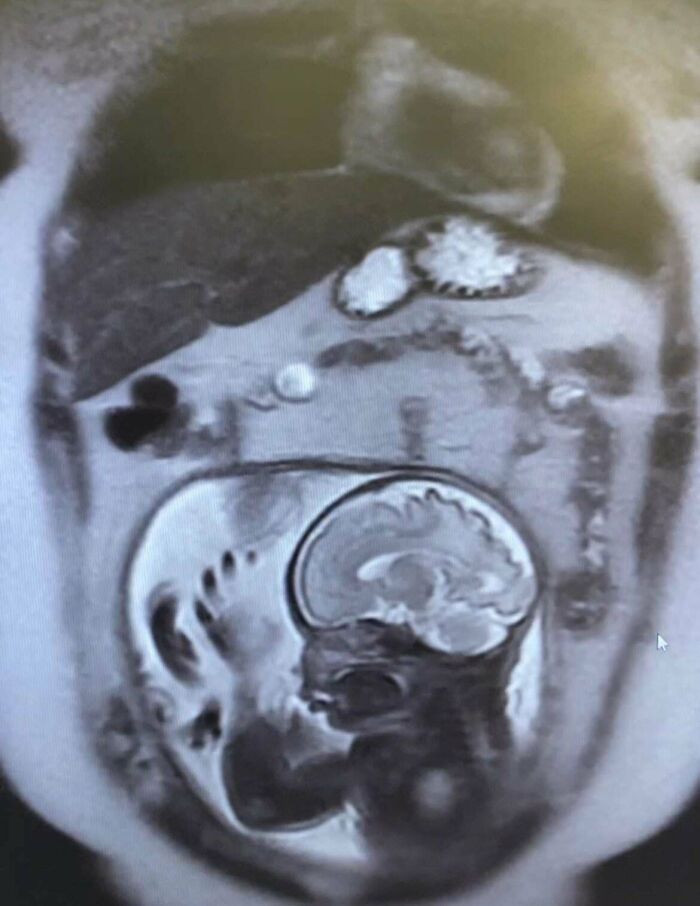

Nietypowy widok z rezonansu magnetycznego